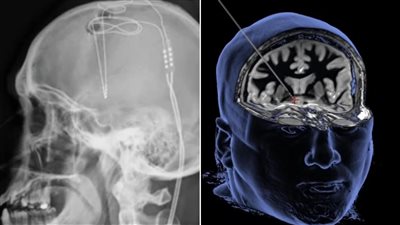

باحثون يكتشفون طريقة فعالة لعلاج الإدمان عن طريق الموجات فوق الصوتية | دراسة